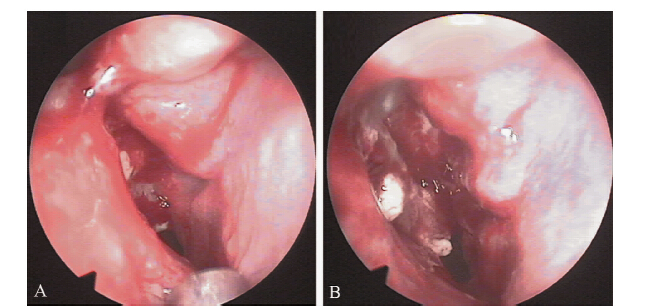

因为患者有持续鼻腔出血和鼻塞,予完善鼻咽部MRI平扫+增强和鼻内窥镜检查。 鼻咽部MRI显示鼻咽中可见软组织信号影填充,范围约23 mm×18 mm(图 3)。 鼻内窥镜检查发现右嗅裂可见一隆起灶,可见局部骨破坏及坏死组织(图 4)。鼻咽部肿物活组织检查显示异形淋巴样细胞弥漫或散在分布,核分裂易见。免疫组织化学结果为CD3(+ + +),CD56(+ + +),TIA-1(+ + +),CD79a(+),LCA(+ + +),Vim(+ + +),CD8(散在+),CD4(散在+),MPO(稀少+),Ki-67 50%(+),而CD20和CD23为阴性。EB病毒编码的小RNA(EBER)原位杂交检测呈阳性(图 5)。骨髓穿刺和脑脊液涂片检查未提示淋巴瘤浸润。外周血未见肿瘤细胞。胸部CT扫描未见异常。

图 3 结外鼻型NK/T细胞淋巴瘤患者鼻咽部MRI扫描 A:T2WI可见鼻咽部有一大小约23 mm×18 mm肿块;B:在化学治疗的第2个疗程时,T2WI可见鼻咽部肿块缩小至11 mm×3 mm |

图 4 结外鼻型NK/T细胞淋巴瘤患者鼻内窥镜检查 A:鼻咽上壁增厚;B:右嗅裂可见一隆起灶,可见局部骨破坏及坏死组织 |